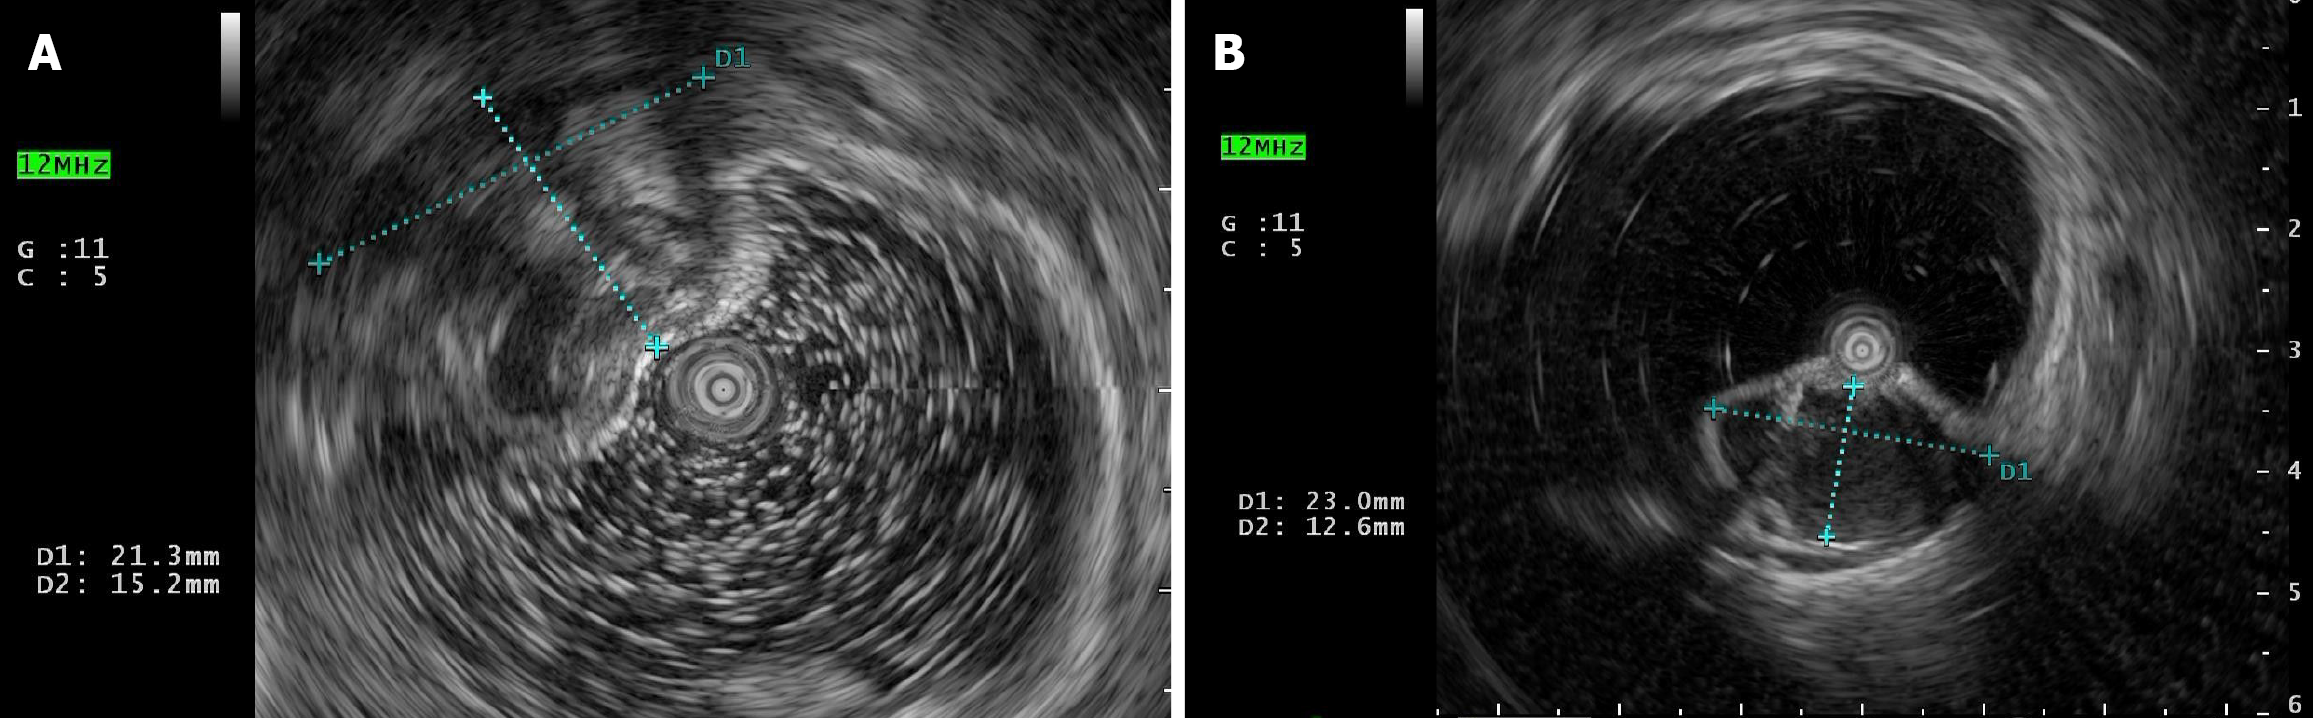

Colonoscopy revealed two large submucosal mass 20 cm and 18 cm from the anal verge (Figure 1). Endorectal ultrasound revealed two cystic mass was observed at the 20 o'clock direction in the left lateral position, in the intrinsic muscular layer and submucosal layer of the sigmoid, with a size of 23.0 mm × 12.6 mm and 21.3 mm × 15.2 mm in diameter, regular morphology, clear boundary, protruding into the lumen, with poor internal transmission and heterogeneous echogenicity or anechoic echogenicity (Figure 2). No abnormalities were found in the physical exam of the patient, and his laboratory tests, such as routine blood work and tumor markers, were within normal limits. Computed tomography (CT) scan of the abdomen displayed an irregular focal thickening of the rectosigmoid wall, with mild to moderate enhancement (Figure 3).

With advances in endoscopic ultrasonography (EUS) technology, this method is crucial for pre-surgical diagnosis. It has been reported that there are three main forms of CCP in EUS: (1) Anechoic; (2) Mixed echoic; and (3) Hypoechoic. Under EUS, the typical imaging features of CCP were that the lesions originated from the mucosa or submucosa, and gradually extended to the submucosa or muscularis propria. The echoic area is observed with no color flow imaging. The primary differential diagnosis is mucinous carcinoma, which showed abundant blood flow signal. EUS enables clear identification of the intestinal wall’s distinct layers and assessment of the integrity of the mucosal, muscularis propria, and serosal layers. While EUS cannot definitively diagnose, it is crucial to rule out malignant tumors. Moreover, EUS can be repeated as a follow-up examination. EUS remains there commended as a follow-up management examination. It is easy to perform safe, noninvasive, nonradioactive and well tolerated. In this study, EUS revealed submucosal cystic lesions in both cases, with intact mucosal and serous layers. On CT, CCP manifests as a non-infiltrating submucosal mass with well-defined borders and variable-sized cystic lumens[4]. Magnetic resonance imaging showed low signal on T1-weighted imaging, a submucosal high-signal nodule on T2-weighted imaging, no obvious enhancement on contrast-enhanced sequences, high signal on diffusion-weighted imaging, no diffusion restriction on apparent diffusion coefficient, and marked high signal on T2-weighted imaging - consistent with mucin-containing lesions[7]. Even though colonoscopy provide the benefit of taking biopsies, misdiagnosis can occur when the biopsy depth is limited and the sampling is not enough[4]. Wang et al[8] reported viscous yellow fluid was seen flowing from the lesion during endoscopic resection. Examination of shed showed the presence of neutrophils, lymphocytes, columnar epithelial cells and squamous cells. In our case, the yellow fluid was aspirated by an assistant, and the surgeries were completed uneventfully. This is similar to the study by Wang et al[8]. Ultimately, the definite diagnosis of CCP was eventually determined based on the operative findings and postoperative pathology.